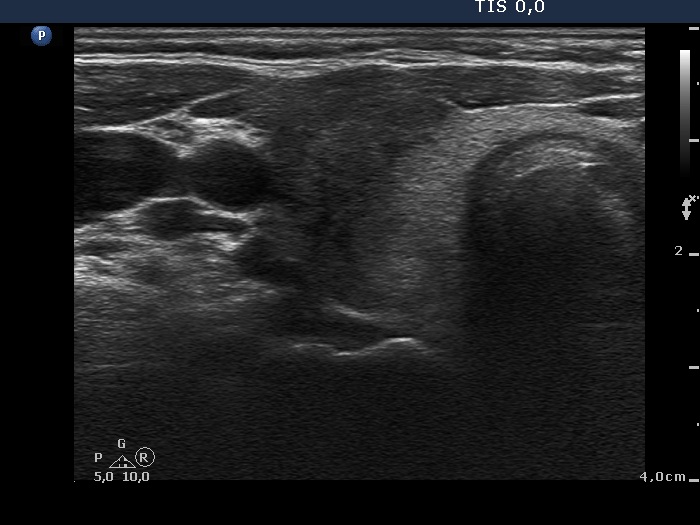

Initial examination (first row of images):

Clinical presentation: A 39-year-old woman was referred for evaluation of neck complaints lasting for more than a month. The patient had fever, neck pain. She has got two courses of antibiotics and non-steroid anti inflammatory drugs which had no effect.

Palpation: The right lobe was painful and hard while the left lobe was tender.

Laboratory examination: TSH 0.01 mIU/L, FT4 29.1 pM/L, FT3 7.45 pM/L, CRP 31.2 mg/L.

Ultrasonography: The thyroid presented with hypoechoic areas which had blurred borders. The echogenicity index was approximately 65% in the right and 20% in the left lobe. The thyroid was almost completely avascular.

Diagnosis: subacute, granulomatous de Quervain's thyroiditis.

Suggestion. Steroid therapy was suggested.